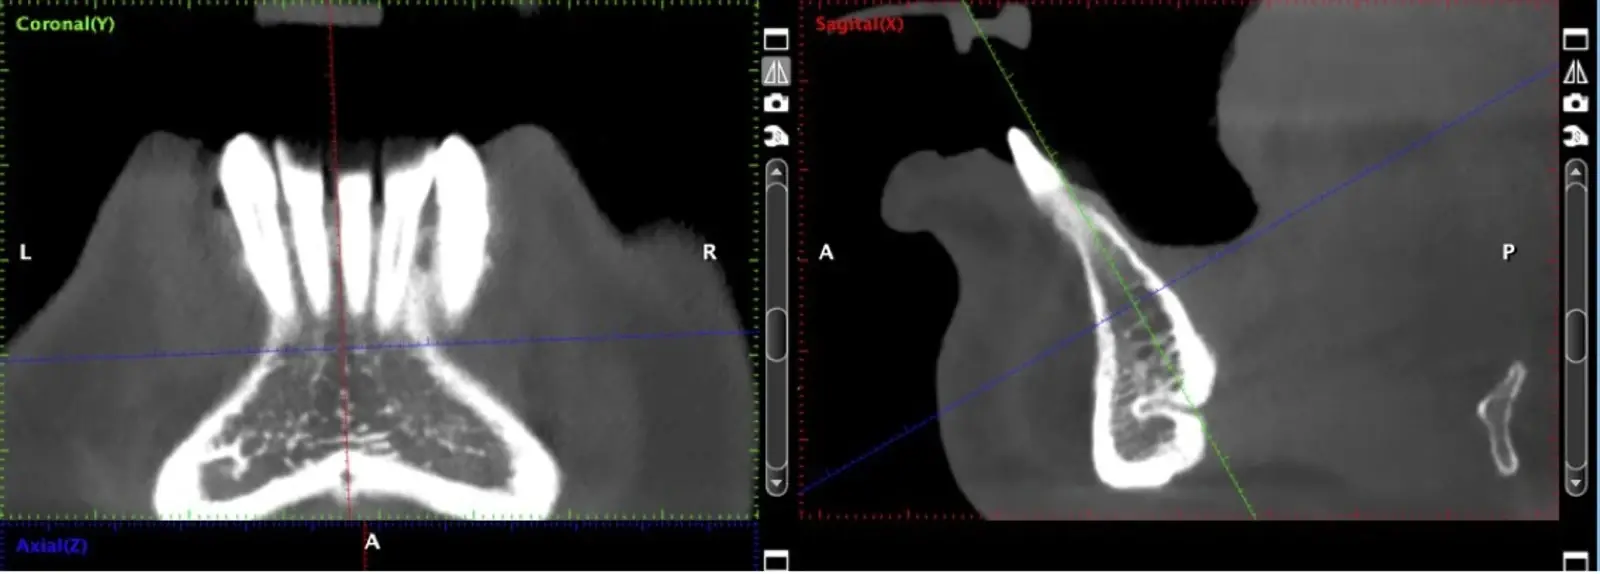

El uso de vibraciones ultrasónicas se introdujo por primera vez hace dos décadas para superar las limitaciones de la instrumentación tradicional.12,13 Altiparmak y cols.14 reportaron en su estudio que la cirugía piezoeléctrica redujo significativamente la incidencia de alteraciones sensoriales tanto de la piel como de la mucosa oral, y redujo también el daño pulpar en los dientes adyacentes, sobre todo en los injertos sinfisiarios.

La osteotomía con insertos de piezoeléctrico nos permite un corte más definido con menor pérdida de hueso residual, ya que los insertos son extremadamente finos.

El uso de los insertos de piezoeléctrico proporciona claras ventajas en la recolección y manipulación de injertos óseos para la reconstrucción de zonas que recibirán implantes dentales.16,17